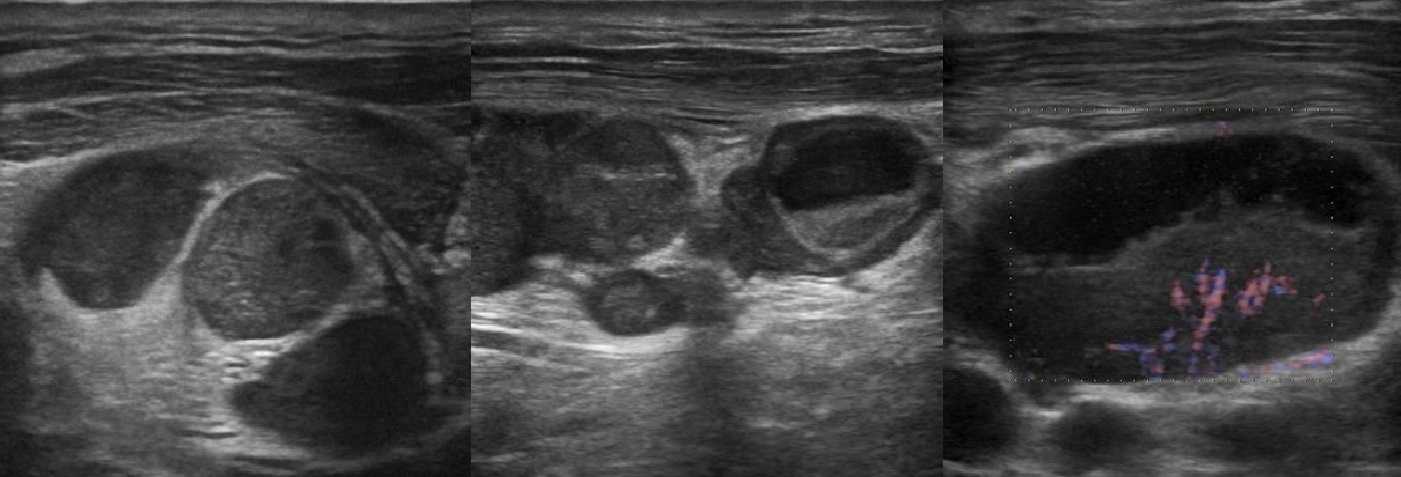

Рисунок. Мальчик 6-ти месяцев с выраженным дерматитом. На УЗИ шейные (1) и подчелюстные (2) лимфоузлы увеличены, вытянутой формы, гипоэхогенные по периферии с гиперэхогенной линейной структурой в центре

Обратите внимание подчелюстной лимфоузел с волнистым контуром. Заключение: Лимфаденопатия шейных и подчелюстных лимфоузлов

Рисунок. Ребенок с высокой температурой, ангиной и двусторонней «опухолью» на шее, в общем анализе крови атипичные мононуклеары 25%. На УЗИ передне- и заднешейные лимфоузлы увеличены (максимальный размер 30х15 мм), округлой формы, неоднородные

Обратите внимание, центральный рубчик отлично видно, а кровоток на уровне ворот усилен. Заключение: Лимфаденопатия с признаками высокой степени активности

Большие группы увеличенных лимфоузлов на шее характерны для инфекционного мононуклеоза. Учитывая течение болезни и наличие атипичных мононуклеаров, вероятно, у ребенка инфекционный мононуклеоз.